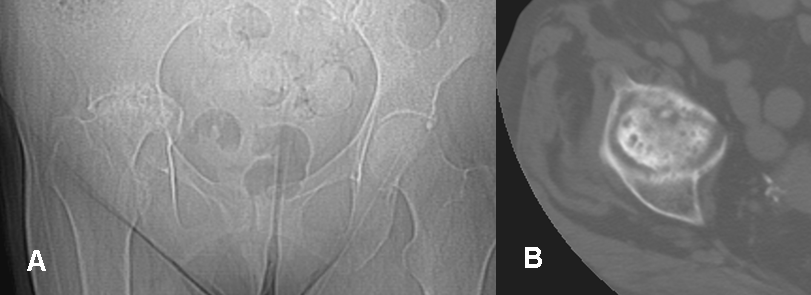

Fig 58 A. Artritis crónica.

A: Rx AP y B: TAC axial. Secuelas de artritis séptica con destrucción de la cabeza femoral y aplanamiento de la cavidad acetabular.

Fig 58 B. Artritis crónica.

A: Rx AP, B: TAC reconstrucción coronal y C: TAC axial. Secuelas de artritis séptica. Pérdida de la cabeza femoral, con luxación posterior del fémur. El espacio articular está ocupado por tejido blando.